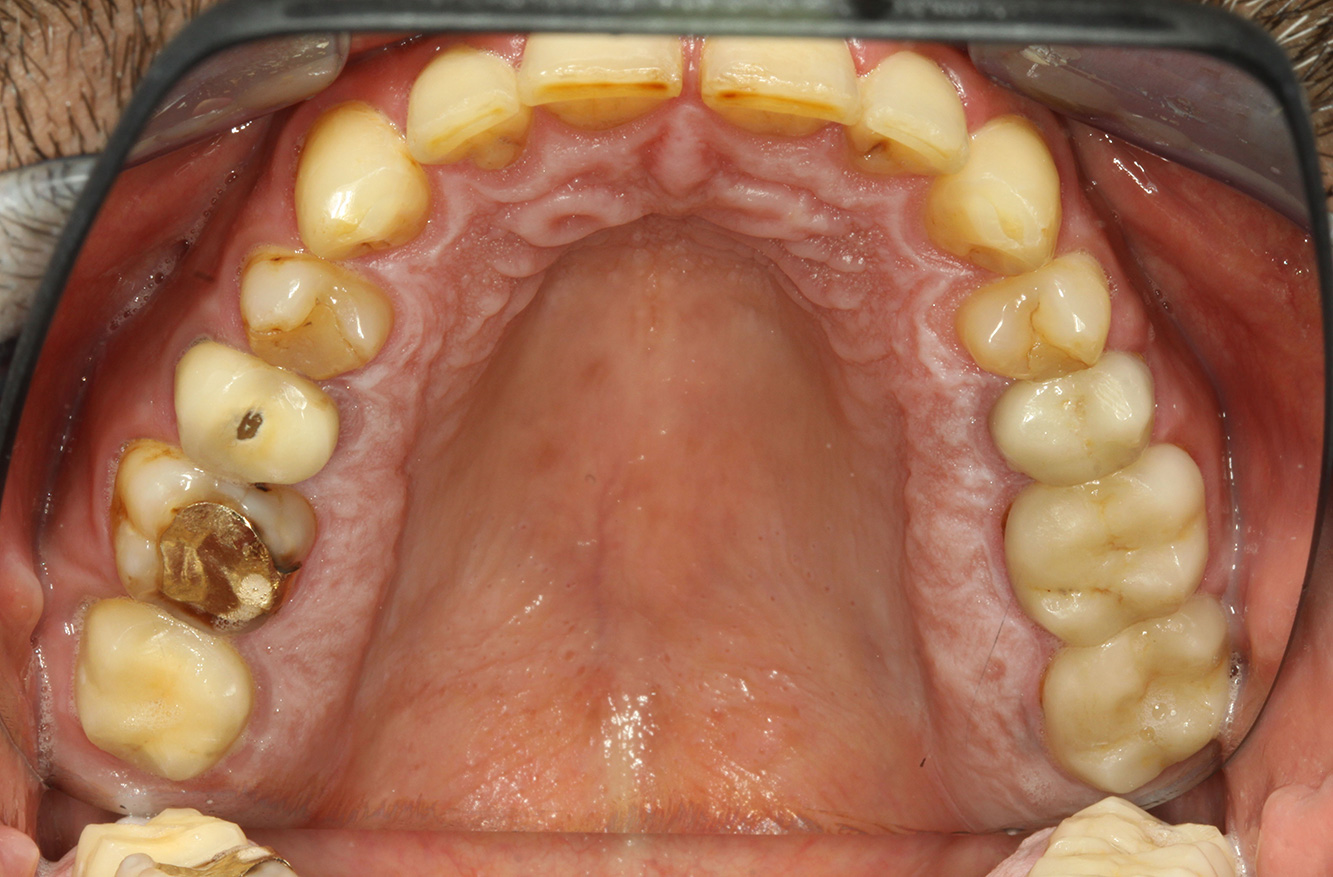

The endocarditis patient with active caries lesions*

The patient is 39 years old and has previously undergone aortic valve replacement due to valve failure and endocarditis. ASS 100 is taken regularly as an anticoagulant. In terms of lifestyle, the patient’s diet is classified as caries-promoting due to the regular consumption of sugary foods and the fact that six to seven meals are consumed daily. The patient’s oral health indicates a moderate risk of caries, with active lesions. The risk of periodontitis is low, but gingivitis is present. The following recommendations are made for prophylactic treatment.